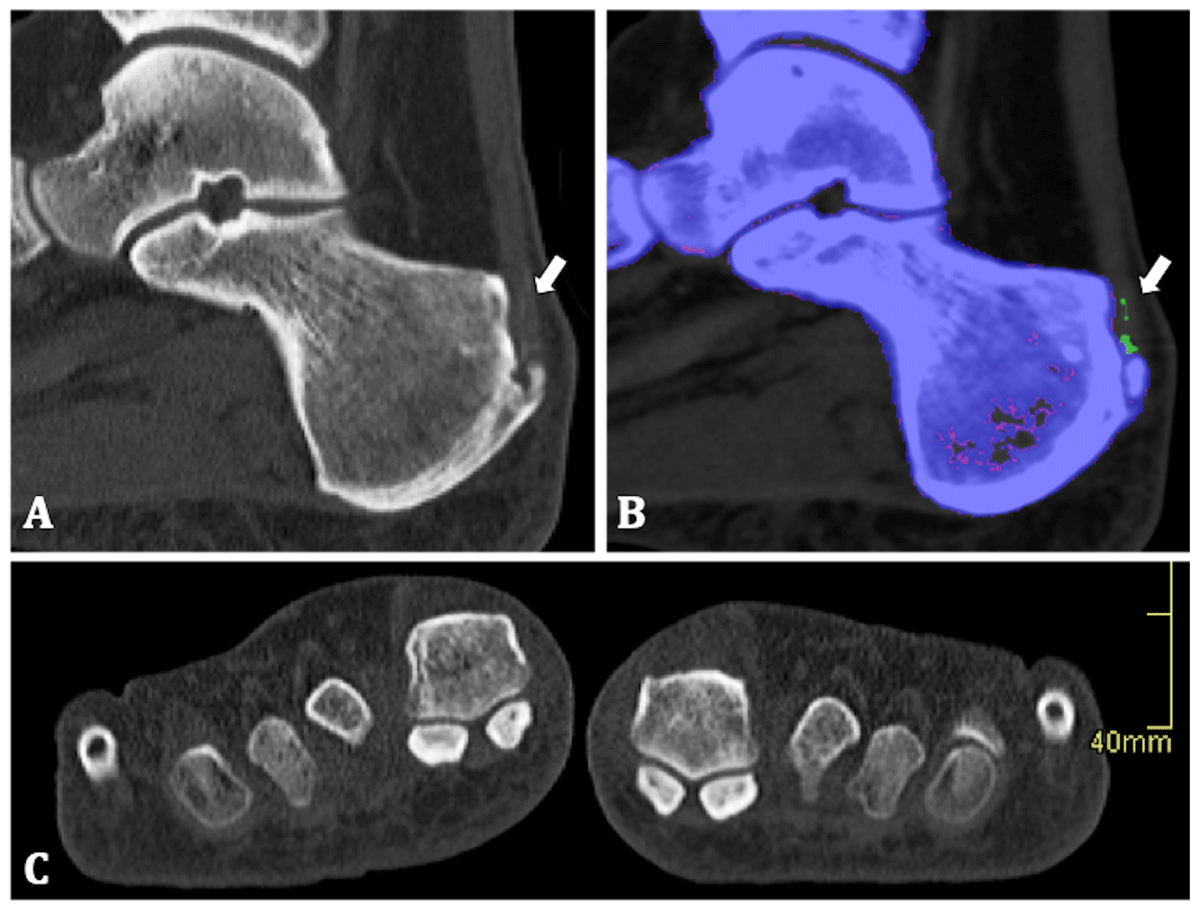

Native CT images showed calcaneal enthesophytes and high-density zones in the right Achilles tendon at the insertion with the absorption spectrum of MSU crystals. The patient had no joint degeneration or erosions in neither of the feet (Figure 2). Nevertheless, the patient could be diagnosed with gout and MSU crystal deposition in the Achilles tendon.

Figure 2

50-year-old man. (A) Sagittal native CT image of the right calcaneum. Calcaneal enthesophyte and several linear areas of high density in the Achilles enthesis are shown (arrow). (B) Colour-coding identifies the linear densities as uric acid crystals (arrow). (C) Coronal native CT image shows there were no erosions of the MTP-I.